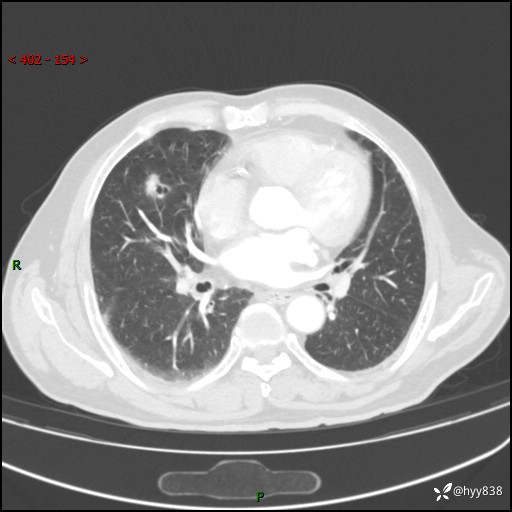

现病史:患者4月前无明显诱因后背正中间疼痛,间断阵痛,无低热、咳嗽,盗汗、咯血、胸痛、喘气等不适,2024-2-25当地市第二人民医院胸部CT提示“1.双肺感染病变;2.右肺中叶结节灶;3.双肺肺气肿并肺大泡4.主动脉及冠脉硬化,今为求明显结节性质遂来我院门诊就诊,门诊以“肺占位”收治入院。 起病以来,患者精神饮食睡眠一般,大小便正常,体力体重无明细变化。

胸部CT平扫(2024.2)